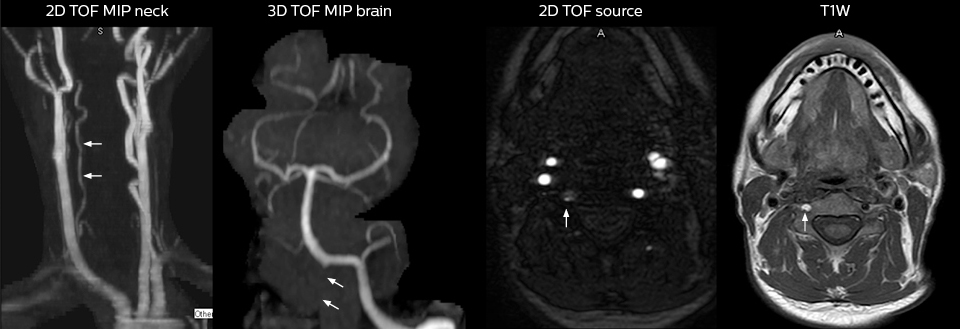

cervical spine mri in ed

Cervical spine routine exam

This patient presented with headache that was worse with neck flexion and we see a Chiari 1 malformation with low-lying cerebellar tonsils as well as some degenerative cervical thrombolytic change.